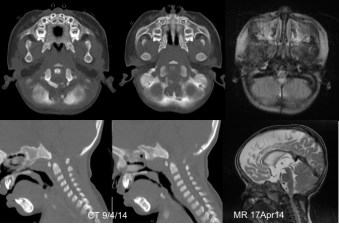

la sténose du foramen occipital de l’achondroplasie

il s’agit d’un problème squelettique lié à la croissance, et non un engagement tonsillaire par mécanisme hydraulique : ce n’est pas une malformation de Chiari.

elle se manifeste le plus souvent dans la petite enfance, avec une compression de la jonction bulbo-médullaire, qui entraine une paralysie avec hypotonie et syndrome pyramidal, des troubles de la déglutition et des troubles respiratoires avec syndrome d’apnées du sommeil de type central. il existe de ce fait un risque de mort subite. il faut s’assurer par l’enregistrement polysomnographique de l’existence d’un syndrome d’apnées du sommeil centrales (par compression de la moelle allongée), obstructives (par rétrécissement des voies respiratoires ou paralysie des nerfs crâniens) ou mixtes.

il peut être nécessaire de décomprimer le foramen occipital (ci-dessus) mais aussi de dégager les voies respiratoires supérieures (résection des végétations adénoïdes, parfois de faire une chirurgie d’avancée faciale avec distraction. C’est donc une prise en charge pluridisciplinaire.